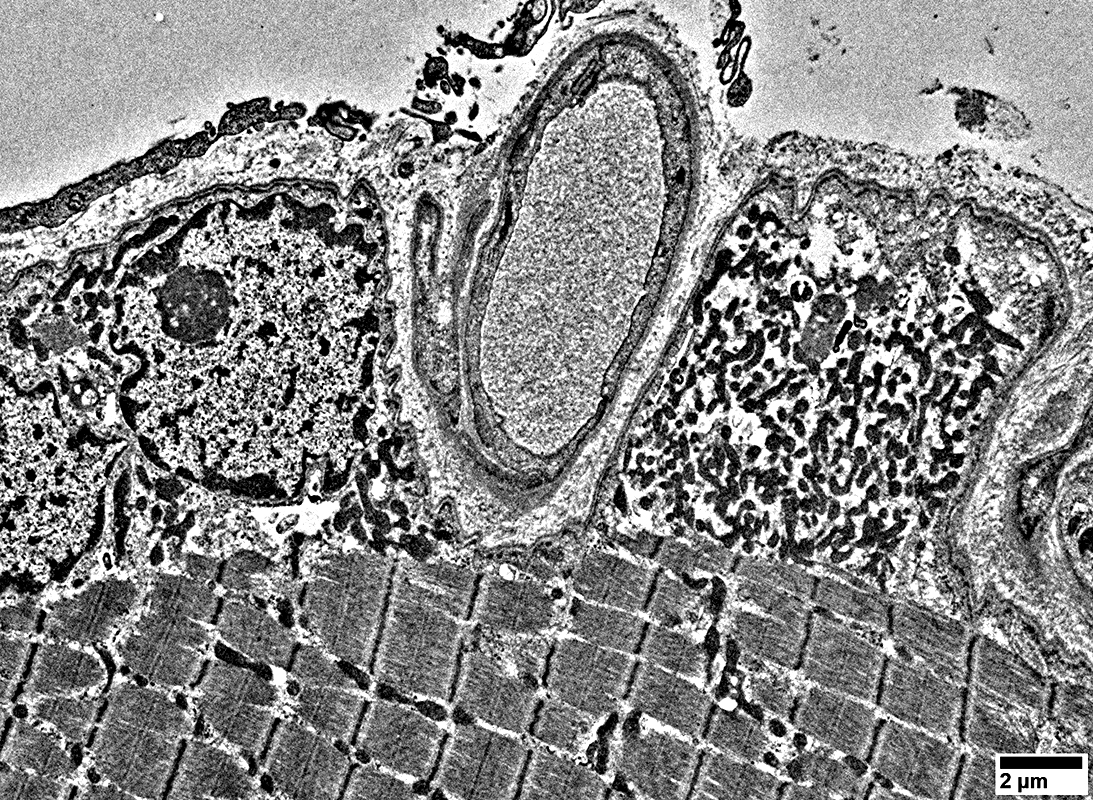

Mitochondrial myopathy: Subsarcolemmal accumulations of mitochondria

Mitochondrial myopathy: Enlarged whorled mitochondrion